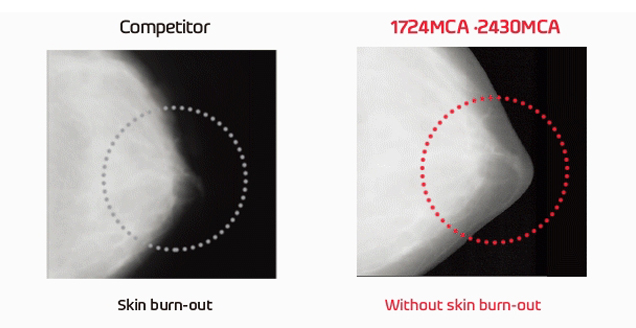

피부 표현 극대화, 미세석회화 증폭 기술을 통한 병변 검출 효과 향상